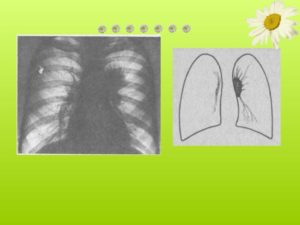

— Туберкулез лимфатических узлов. Картина меняется в зависимости от того, идет ли речь о цветущем (первичном или вторичном) туберкулезе или о старых зарубцевавшихся, часто обызвествленных, излеченных формах.

Для цветущего туберкулеза прикорневых лимфатических узлов характерны резко отграниченные клубневидные прикорневые узлы, одно- или двусторонние.

В некоторых случаях еще виден в легких первичный очаг, в других случаях — только усиленный рисунок на ограниченном месте.

Иногда же легочного очага вообще уже не видно. Такую картину иногда трудно отличить от саркоидоза и, поскольку еще не известно течение процесса, от опухолей, особенно от лимфогранулематоза. В таких случаях диагноз приходится ставить почти только путем исключения.